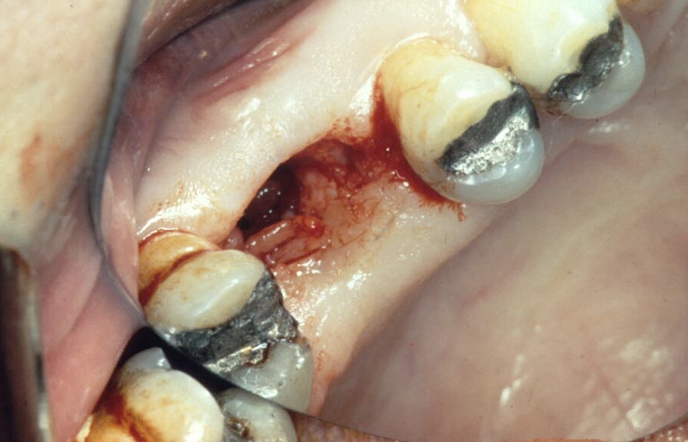

how can you tell this is an oac

still bleeding so must just been made